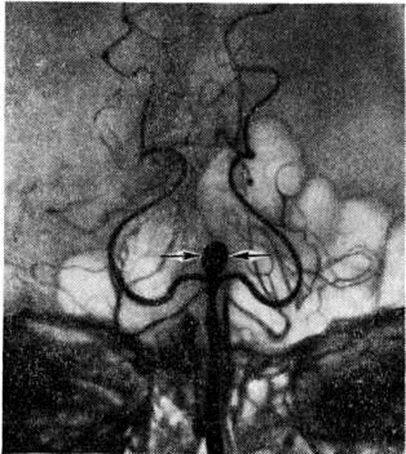

Анатомия: Задняя соединительная артерия мозга

:max_bytes(150000):strip_icc()/CircleofWillis-87378170-3ece0502a02949dd82310d723e0d4c98.jpg)